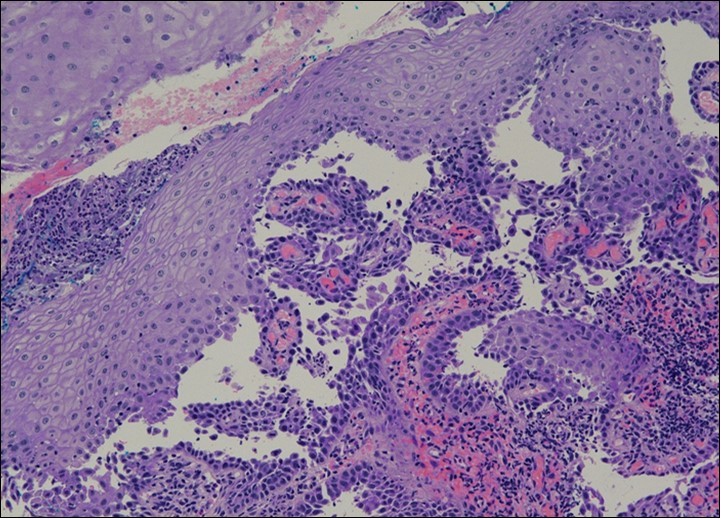

She was discussed at the hospital cyto-pathology conference to clarify the diagnosis. The original cytological smear specimen was reviewed, with features of bi-nucleation and koilocytosis consistent with LSIL. The cervical biopsy was also reviewed, confirming typical features suggestive of cervical pemphigus. (Figure 4a, Figure 4b, Figure 4c)

Figure 4a.Cervical tissue showing intraepidermal and supra-basal blister formation.

Cervical tissue showing intraepidermal and supra-basal blister formation.

Figure 4b.Prominent acantholysis identified

Prominent acantholysis identified